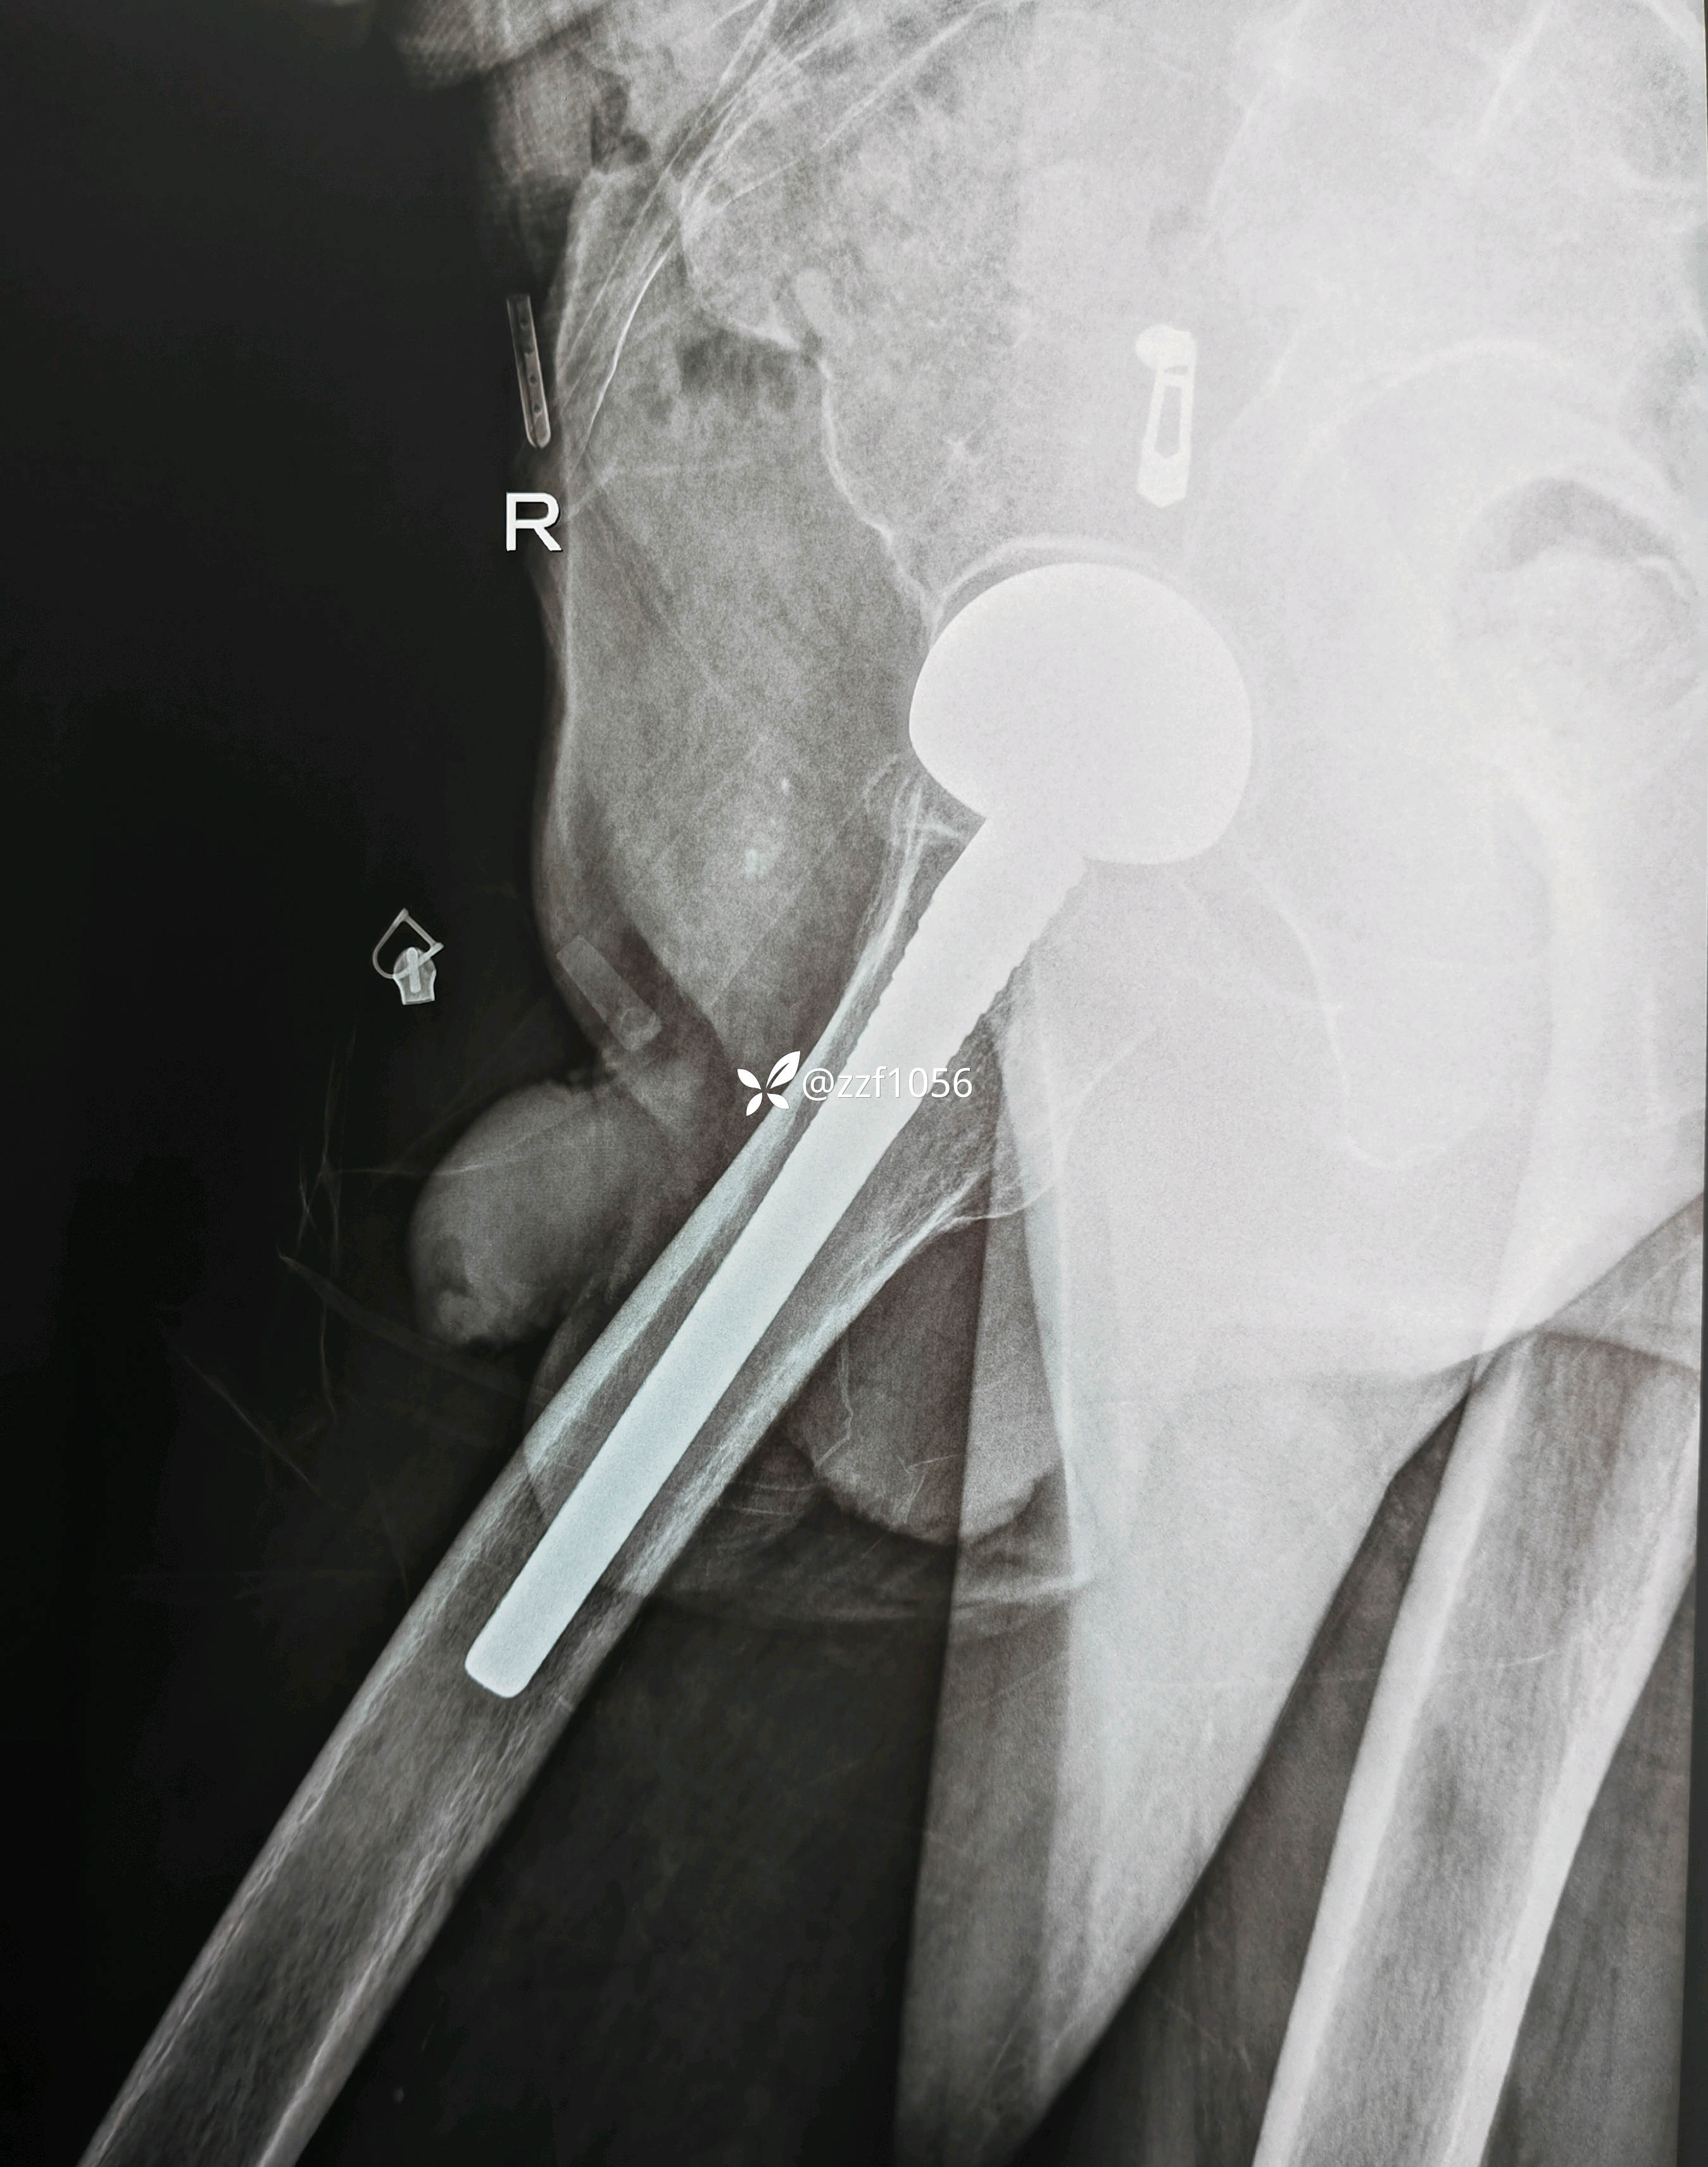

患者男80岁,摔伤右髋疼痛5天,入院。

5天前家里摔伤,附近医院摄片显示右侧股骨颈骨折,因身体状况不好回家保守治疗,疼痛无法耐受再次赴当地县医院就诊,评估身体状况后告知手术风险较大,后经熟人介绍转来我院就诊。

入院诊断:右侧股骨颈骨折

顺利实施手术双动头置换